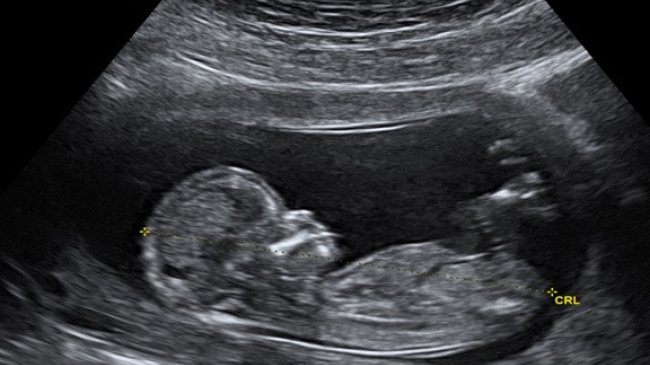

Un cuplu din Alabama a aflat că familia lor se mărește cu două persoane. Nimic anormal până aici. Doar că fiecare copil crește în propriul uter, scrie stirileprotv.ro.

Mama lor știa că are două organe de reproducere, dar nu s-a așteptat în niciun moment să poarte câte un copil în fiecare dintre ele. Cazul este atât de rar, încât medicii americani plănuiesc să facă un studiu pe baza lui.

Kaley și-a lăsat medicul fără cuvinte la consultul care i-a confirmat sarcina. Cei doi embrioni se aflau, fiecare, în propriul său uter.

Femeia știa că are două utere, fiecare cu propriul col uterin, dar nu i-a trecut niciodată prin minte că ar putea să poarte câte un bebeluș în fiecare.

Richard Davis, medic obstetrician: „Trei la o mie de femei pot avea asta (uter dublu). Posibilitatea de a avea câte un copil în fiecare e ceva nebunesc”.

Shweta Patel, medic obstetrician: „Din punct de vedere medical, e un caz atât de rar, că nici nu știm cum să numim acești bebeluși, așa că le zicem gemeni”.

Până acum, sarcina a decurs normal. Provocarea va fi când unul dintre utere se va contracta, pregătind nașterea.

Termenul nașterii e în jurul Crăciunului. Medicii spun că bebelușii, două fetițe, ar putea să vină pe lume în zile sau chiar săptămâni diferite.